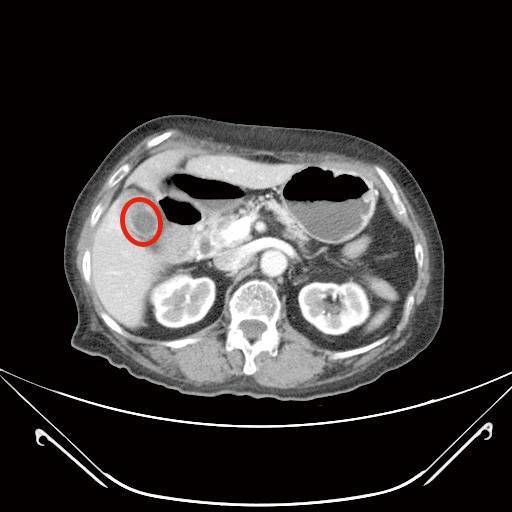

▲患者胃腸道基質瘤已經有6公分大小。(圖/國泰醫院提供)

72歲林女士,3年前經上消化道內視鏡檢查發現有個2公分大的胃黏膜下腫瘤,疑似胃腸道基質瘤,持續門診追蹤,近期發現腫瘤緩慢長大,2個月前因上腹部悶痛且頭暈就診,由於合併有血便症狀,經上消化道內視鏡及電腦斷層檢查,發現腫瘤已接近6公分大,同時膽囊被結石塞滿,已經沒有膽汁的空間,最後透過微創手術進行部分胃切除以及膽囊切除,一次完成治療。

蔡欣恬指出,胃腸道基質瘤手術的目標在於完整將腫瘤切除,以往這類患者需接受超過15公分傷口的剖腹手術(傷口位於腹部正中間),考量病人合併有膽結石問題,所以建議接受達文西系統機器手臂輔助腹腔鏡手術,不但可以做更細緻的剝離及切除,也可同時處理胃部惡性腫瘤及膽結石。